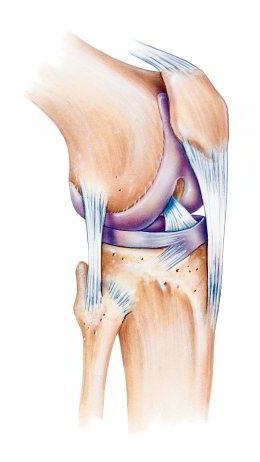

Kniescheibe mit

Bändern, Schema Seitenansicht Kniescheibe mit Bändern, Schema Seitenansicht [2] und von vorn [3]

-- die Kniescheibe ist eine etwas dreieckige Scheibe mit Wölbung zum Schutz des Knies

-- die Kniescheibe wird von Sehnen oben und unten gehalten, oben am Oberschenkelmuskel angesetzt, unten am Schienbein angesetzt

-- dank der Kniescheibe und den Sehnen kann man das Bein in leichter Weise strecken

-- die Rückseite der Kniescheibe hat eine Knorpelschicht für das Gleiten beim Beugen und Strecken des Beines

-- im Alter bildet sich die Knorpelschicht zurück, so beginnt oft eine Kniearthrose

-- Schäden an der Kniescheibe können sein: Fehlbildung, Bruch, Entzündung [web01]

Knie mit Kniescheibe mit

Bändern, Vorderansicht

Schema Knie Querschnitt

Knie Schema mit dem Querschnitt [x1]